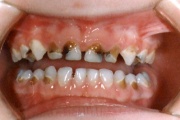

Laste ja noorukite söömishäired. Anorexia nervosa, Bulimia nervosa

amelogenesis imperfecta

Emaili hüpoplaasiad

Hamba atritsioon